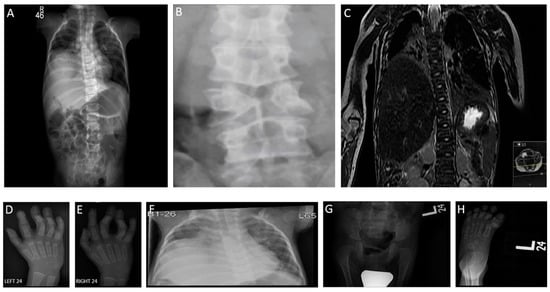

3.1.1. Patient 1 (Family 1)

3.1.2. Patient 2 (Family 2)